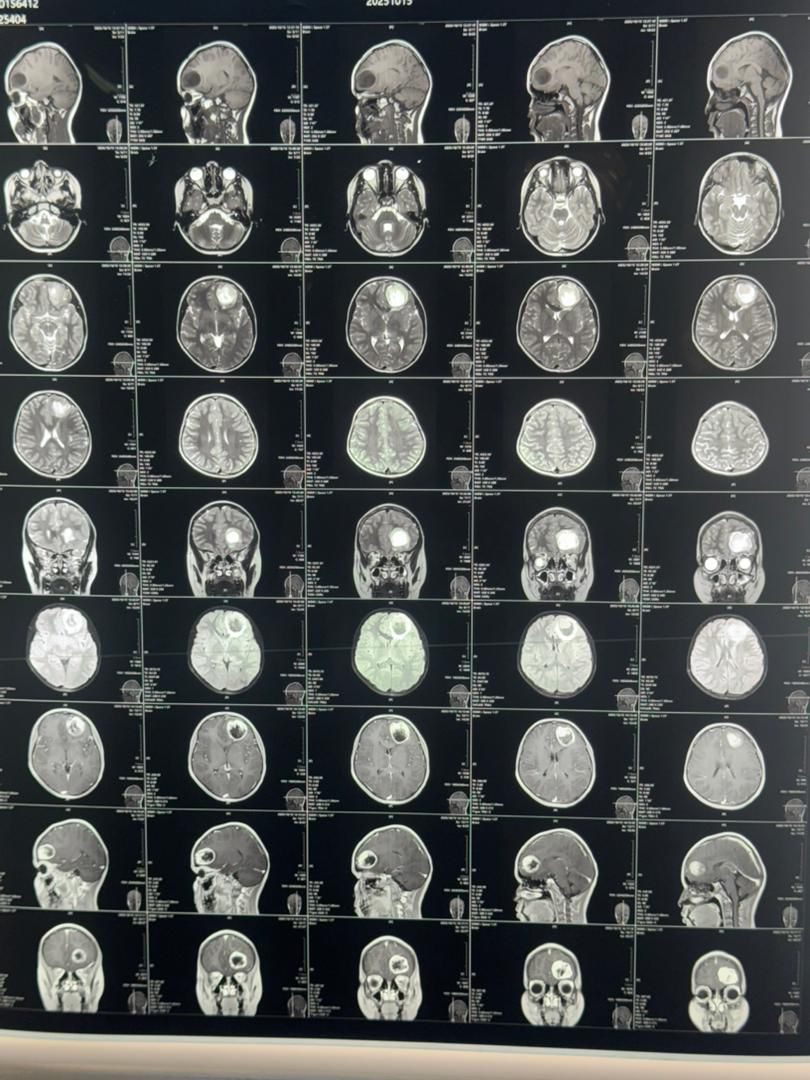

د ياد روغتون د اعصابو جراحي څانګې مسؤلينو خبر ورکړ، چې د دماغ دننه (Intra-axial) تومور لومړني جراحي عمليات، چې د يوې ۱۲ کلنې نجلۍ د شديد سر درد، زړه بدوالي او د ليد کمښت لامل شوی و، په برياليتوب سره ترسره شول.

دغه پنځه ساعته جراحي عمليات د ابو علي سينا حوزوي روغتون د اعصابو جراحي ټيم له لوري د عصري جراحي وسايلو په کارولو سره ترسره شول، چې ناروغه تر يوې اوونۍ بستر کېدو او درملنې وروسته په بشپړه روغتيا سره رخصت شوه.